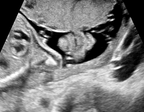

We further present correctly classified and mis-classified examples of using MIDNet in Fig. 11 (b).

| Femur | Lips |

|

\stackunder Femur |

\stackunder Lips |

\stackunder Abdominal |